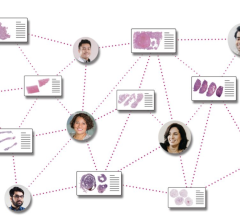

March 21, 2023 — Pramana, Inc., an AI-enabled health tech company modernizing the pathology sector, and PathPresenter ...

Having the most efficient clinical workflows with enhanced diagnostic capabilities is a major goal for clinicians and ...